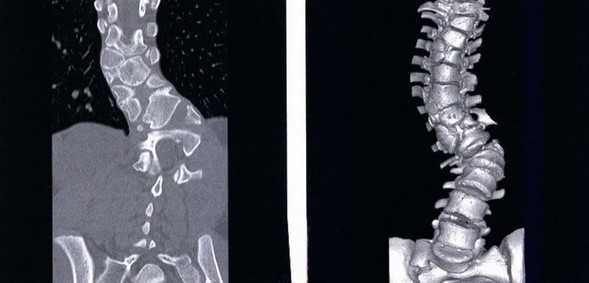

Перелом грудного отдела (трехмерная и сагиттальная проекции)

В результате компьютерной томографии получают серию послойных изображений рассматриваемой зоны. Монохромные фотографии обладают высоким разрешением. В отличие от рентгенографии на снимках отсутствуют дефекты и тени от расположенных рядом структур. Изменение плоскости при реконструкции изображений позволяет тщательно изучить анатомические образования. Преимуществом КТ является возможность создания 3D-модели позвоночника.

Компрессионный перелом (показан стрелкой) поясничного отдела позвоночника

Трещина (показана стрелкой) тела позвонка